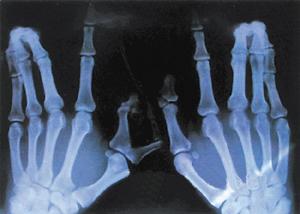

专家表示,软骨发育异常又称内生软骨瘤病,Ollier病等。其特征为,长骨的干骺端有圆形或柱状的软骨性肿块,伴骨干缩短及畸形,在指骨尤为常见。1899年首先由Ollier所描写,虽其组织结构与内生软骨瘤相似,但一般认为本病不应属于肿瘤范围。